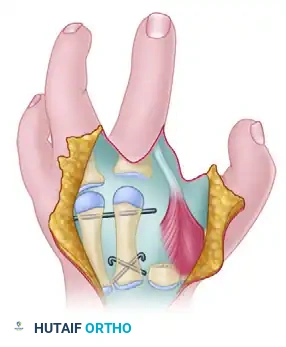

The index finger is transposed following the osteotomy of the index metacarpal base and the release of the first dorsal interosseous muscle.

- If adequate bone stock is present, reduce the osteotomy and fix the index metacarpal to the third metacarpal base using crossed or parallel Kirschner wires (K-wires).

Additional subperiosteal release of the first dorsal interosseous allows tension-free transposition. The inset demonstrates the necessary rotation (up to 45 degrees) required to prevent digital overlap during flexion.

Clinical Pearl: Rotational alignment is the most critical aspect of the osteotomy. The transposed digit must be supinated (often up to 45 degrees) to ensure it flexes symmetrically into the palm without scissoring over the ring finger.